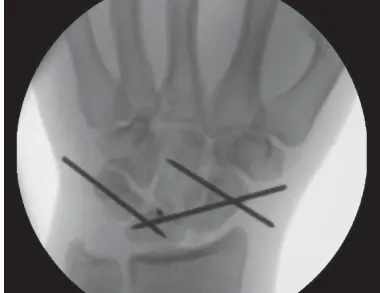

- التثبيت الداخلي (Internal Fixation): استخدام دبابيس معدنية (K-wires) أو مسامير صغيرة لتثبيت العظام في مكانها أثناء فترة الشفاء.

- التقليل المفتوح والتثبيت الداخلي (Open Reduction Internal Fixation - ORIF):

- هو الإجراء الأكثر شيوعًا. يقوم الدكتور هطيف بعمل شق جراحي في الرسغ (عادةً من الظهر أو من الجانبين) للوصول المباشر إلى العظام الرسغية والأربطة.

- يقوم بإعادة العظام المنخلعة إلى مكانها الصحيح تحت الرؤية المباشرة.

- ثم يقوم بإصلاح الأربطة الممزقة باستخدام خيوط جراحية دقيقة.

- يتم تثبيت العظام في مكانها باستخدام دبابيس معدنية رفيعة (K-wires) مؤقتة تخترق الجلد، أو مسامير صغيرة، أو لوحات خاصة. تُزال الدبابيس عادةً بعد 6-8 أسابيع.